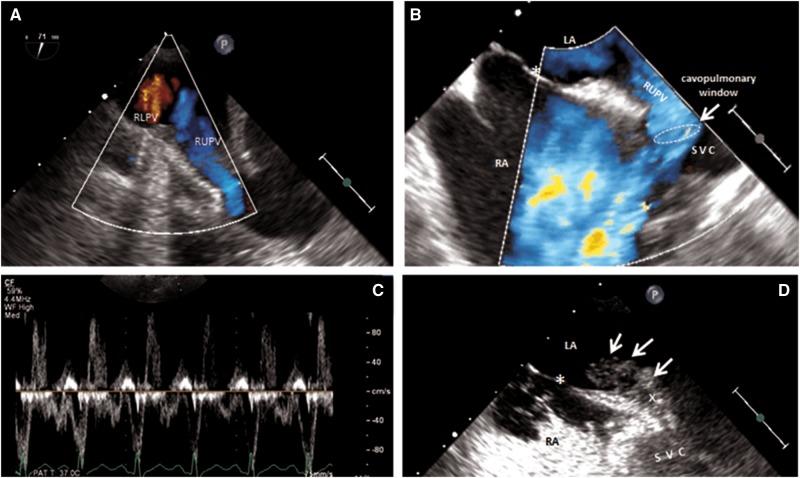

Isolated partial anomalous pulmonary venous return (PAPVR) with intact atrial septum is a rare finding. A cavopulmonary window is a side-to-side veno-venous communication of the right upper pulmonary vein with the superior vena cava which in its course retains connection to the left atrium.

We present a case of this unusual variant of a sinus venosus defect far from the atrial roof. Haemodynamic significance of the shunt was confirmed by enlargement of right heart cavities, elevation of pulmonary artery pressure, and significant left-to-right shunting using multimodality cardiac imaging (transoesophageal echocardiography, cardiac magnetic resonance imaging, and right heart catheterization). The defect has been successfully repaired using minimally invasive axillary thoracotomy.

孤立性部分性肺静脉异位引流(PAPVR)且房间隔完整是一种罕见的情况。腔肺窗是右上肺静脉与上腔静脉之间的左右侧静脉-静脉交通,其在走行过程中与左心房保持连接。

我们报告一例远离心房顶部的静脉窦型缺损的这种不寻常变异病例。通过多模态心脏成像(经食管超声心动图、心脏磁共振成像和右心导管检查)证实右心腔扩大、肺动脉压升高以及显著的左向右分流,从而确定了分流的血流动力学意义。该缺损已通过微创腋下开胸手术成功修复。